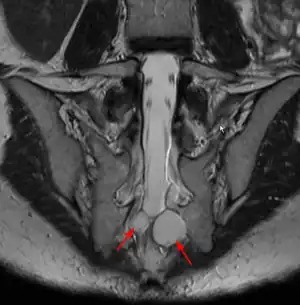

| MRI image showing a Tarlov cyst | |

MRI

MRI, or Magnetic Resonance Imaging, is considered the imaging study of choice in identifying Tarlov cysts. MRI provides better resolution of tissue density, absence of bone interference, multiplanar capabilities, and is noninvasive. Plain films may show bony erosion of the spinal canal or of the sacral foramina. On MRI pictures, the signal is the same as the CSF one.